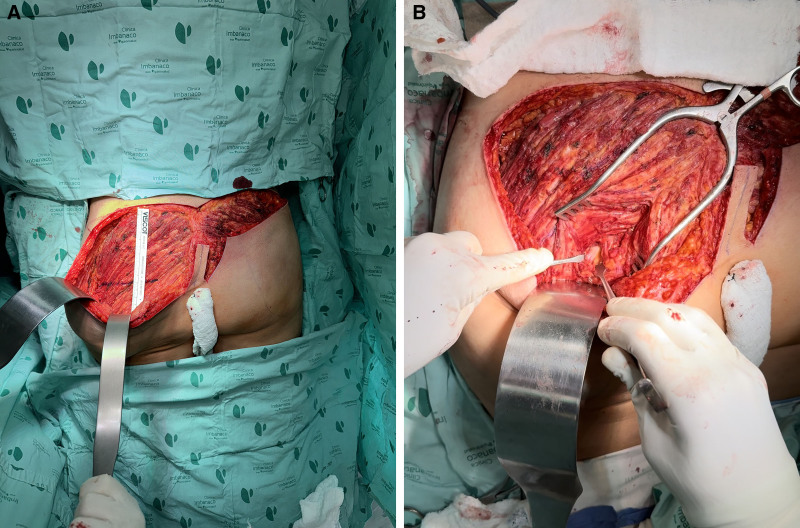

患者有臀区深度注射非药物物质(生物聚合物)的病史,导致坐骨神经受压。本文描述了从皮下组织、肌肉组织和坐骨神经中去除生物聚合物的外科技术。对目前的坐骨神经手术入路进行了结构化的回顾。详细介绍了临床病例的术前评价、术中技术及术后随访情况。所描述的手术入路有效地减压坐骨神经,从皮下组织和肌肉组织中去除生物聚合物材料,并改善症状、美容效果、恢复时间和额外手术的需要。鉴于生物聚合物去除和神经压迫的管理信息有限,该技术代表了一种可行的替代方案,在恢复和美容效果方面都有好处。

The patient presented with a history of deep injection of a nonmedical substance (biopolymer) into the gluteal region, resulting in compression of the sciatic nerve. The surgical technique used to remove biopolymers from the subcutaneous tissue, muscle tissue, and sciatic nerve is described. A structured review of the current surgical approaches for the sciatic nerve was conducted. The preoperative evaluation, intraoperative technique, and postoperative follow-up of the clinical case are detailed. The described surgical approach effectively decompresses the sciatic nerve, removes the biopolymer material from the subcutaneous tissue and muscle tissue, and improves symptoms, cosmetic outcomes, recovery time, and the need for additional surgery. Given the limited information on the management of biopolymer removal and nerve compression, this technique represents a viable alternative, offering benefits in recovery and cosmetic outcomes.